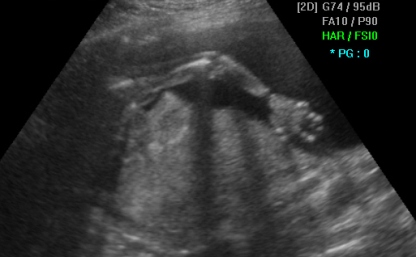

Раката на бебето во 2D ултразвучна техника